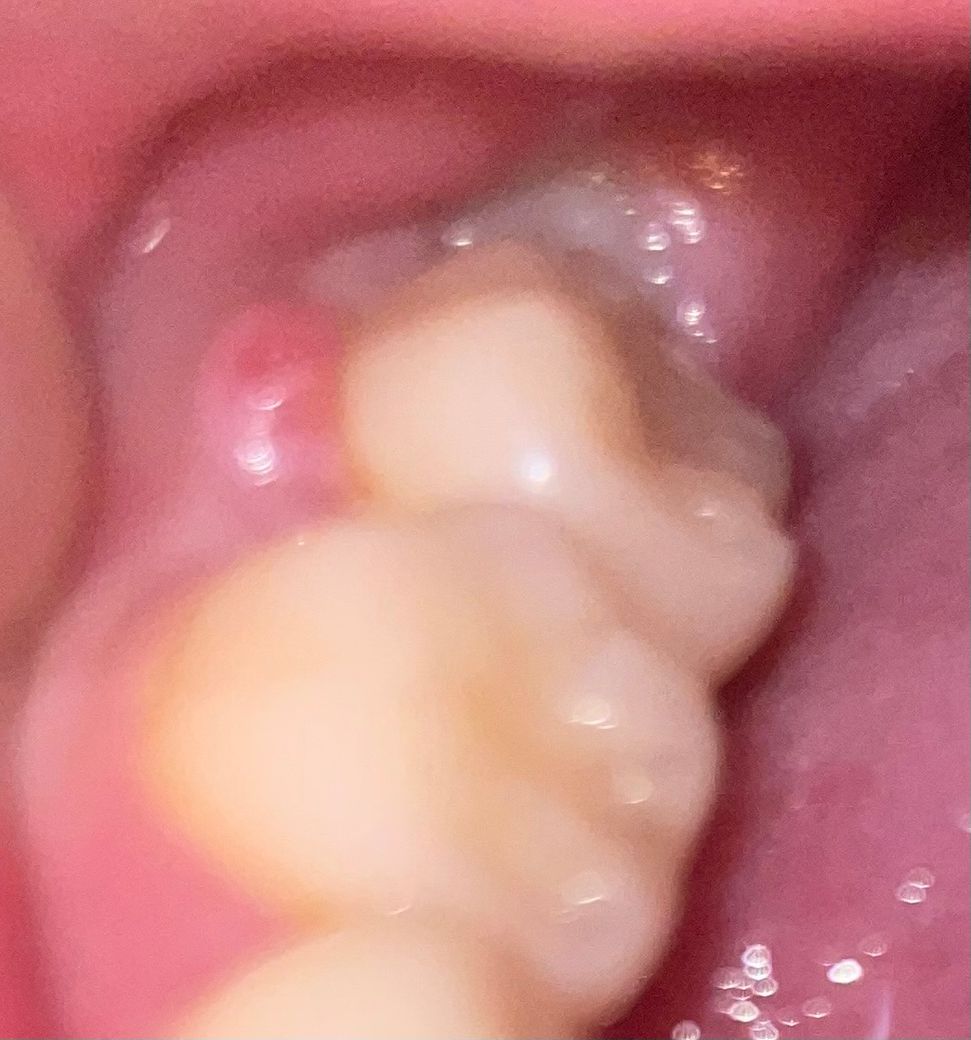

어금니 잇몸 부어서 이물감 있는데 이거 심각한 건가요??

제가 군대 모집병 준비하느라 이것저것해야해서 7월 말까지는 시간이 없어요.. 근데 요 며칠 잇몸이 부었는지 어금니쪽에 이물감이 있더라구요 통증은 없구요..!!! 이거 심각한건가요..비용은 얼마나 될까요 ..치료할때 많이 아플까요

• 1번 째 사진

사진으로 봤을 경우에는 잇몸이 많이 부어 있는 것으로 보입니다 사진과 같이 잇몸이 붙는 원인은 여러 가지 원인이 있을 수 있습니다 이물질로 인한 염증이라면 잇몸 치료를 해야 합니다 파절 등으로 인해서 생긴 증상이라면 해당 치아를 치료해야 할 수 있습니다.

1. 잇몸 부위 염증, 농양이 잡혀 있는 상태로 보이고 원인이 잇몸쪽일 수도 있고, 치아쪽일 수도 있습니다. 잇몸이 원인이라면 잇몸치료, 치아쪽이 원인이라면 신경치료가 필요할 수 있습니다.